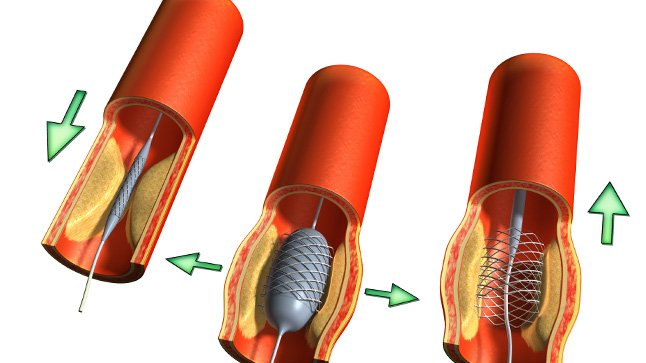

Es un procedimiento mínimamente invasivo que se realiza dentro de los vasos sanguíneos para restituir o aumentar el flujo de sangre.

Se realiza en diferentes vasos sanguíneos: arterias coronarias (irrigan al corazón), arterias periféricas (irrigan los brazos y las piernas), arterias carótidas (irrigan el cerebro).

La intervención consiste en la introducción de un tubo delgado (catéter) a través de una vena o arteria hasta llegar al sitio donde hay una obstrucción causada por una placa de colesterol o un coágulo.

Allí, se infla un balón, colocado en el extremo del tubo, para abrir la luz de la arteria y restaurar el flujo sanguíneo. En algunos casos, se deja colocado un "stent" para que el vaso permanezca abierto.

La angioplastia permite que se normalice la circulación de la sangre (revascularización). No se trata de una cirugía, ya que no se realizan grandes incisiones sino sólo pequeñas punciones. Generalmente, el paciente está despierto o bajo una mínima anestesia.